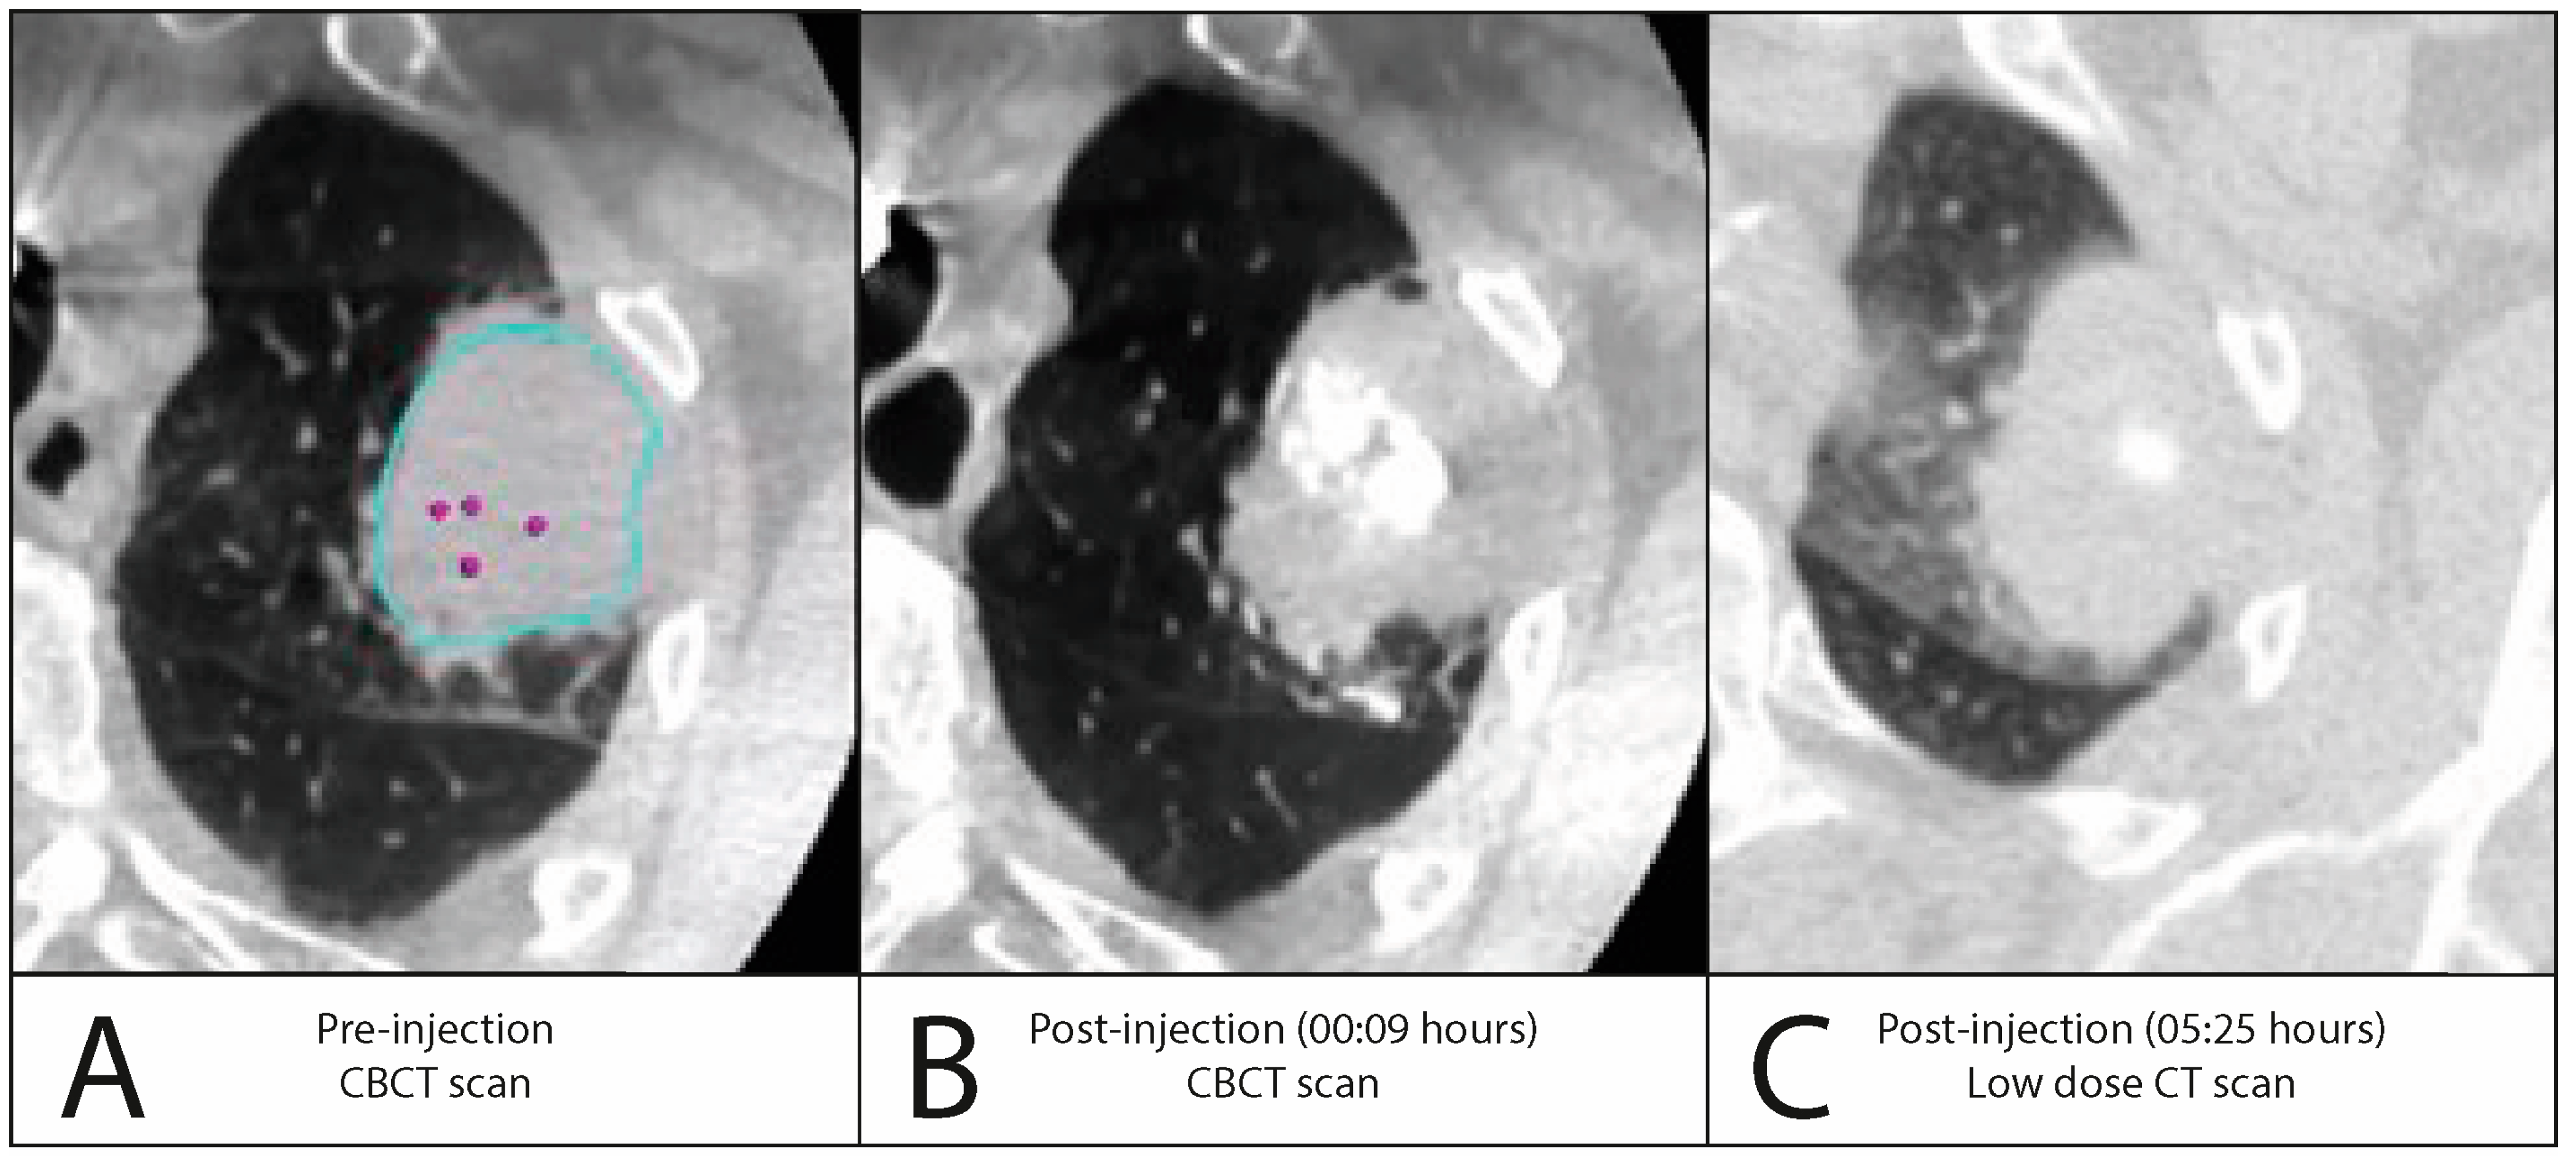

3.2.2. Iodinated Contrast Injection

| Injection volume, mL, median (±IQR) | 0.30 (±0.20) | ||

| Injection visible on fluoroscopy, n (%) | 15 (100%) | ||

| Leakage visible on fluoroscopy, n (%) | 4 (26.7%) | ||